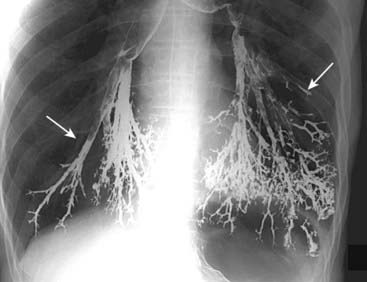

Figure 18-1 Aspiration, barium gone wild.

Frontal radiograph of the lung bases demonstrates high density material outlining the tracheobronchial tree (solid white arrows). The material is barium that was aspirated into the lung during an upper gastrointestinal series. Barium is inert and did not cause any additional symptoms that the patient wasn’t already experiencing from aspirating his own secretions. It will take some time, but most of this barium will be reabsorbed, most likely leaving only a small amount remaining.